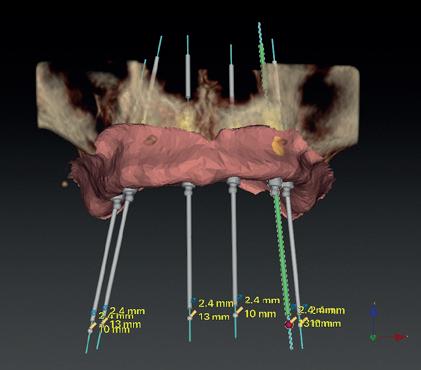

Horizontaal botverlies en mini-implantaten - Een geheel andere anatomische situatie ontstaat bij een meer horizontaal resorptiepatroon. Hierbij blijft de kaakhoogte vrijwel volledig intact, maar neemt de dikte van de processus alveolaris af tot een minimum van slechts enkele millimeters. Indien sprake is van een dergelijke zeer dunne processus alveolaris in de maxilla of mandibula, kan ervoor worden gekozen om gebruik te maken van mini-implantaten (implantaten met een diameter < 2.5 tot 3 mm, afbeeldingen 3a-b), als alternatief op een chirurgische kaakverbreding door middel van ‘buccal plating’ met een autoloog bottransplantaat. Het gebruik van mini-implantaten bespaart de patiënt pre-implantologische chirurgie, lange behandelduur, morbiditeit en de noodzaak tot herhaalde aanpassingen van de prothese. Door mini-implantaten flapless te plaatsen wordt de morbiditeit tot een minimum gereduceerd. Hiervoor is echter wel 3D-planning vooraf een vereiste alsook statische navigatie bij het plaatsen door middel van een dwingende boormal, vanwege de zeer geringe marges (zie casus, afbeeldingen 4a-q ). Een bijkomend voordeel van mini-implantaten is, dat ze uit één geheel bestaan en standaard zijn voorzien van

4a. Navigatie chirurgie met een dwingende boormal

4b. Na plaatsen wordt de boormal gefixeerd met ‘anchor pins’

4c. Voor mini-implantaten hoeft slechts één keer te worden geboord

4d. Uitnemen boormal na het ‘blind’ prepareren van het implantaatbed

een drukknopje. Hierdoor kan in een laatste levensfase eenvoudig nog een overkappingsprothese worden aangepast of vervangen, ook wanneer er geen aanvullende informatie meer beschikbaar is over het implantaatmerk, type en diameter. Mini-implantaten laten goede succes- en overlevingspercentages zien [Bidra en Almas 2013; Shatkin 2012; vanDoorne et al 2020; vanDoorne et al 2021]

voor alle implantaten

4e. Mini-implantaat (Southern Implants, ILZ12D), diameter 2.4 mm

4f. Flapless plaatsen van het 1e implantaat

4g. Door het genavigeerd prepareren is het plaatsen van de implantaten kinderlijk eenvoudig

4h. Direct postoperatief na flapless aanbrengen van 6 mini-implantaten

4i. Implantaat planning in DTX software

4j. Virtuele gingiva kan alleen worden berekend met een goed aanliggende scanprothese

4k. Maximale spreiding van de implantaten wanneer geen augmentatie wordt verricht

4l. Divergentie van de smalle processus veroorzaakt onderlinge

divergentie, dit wordt met 12 graden angulatie van de drukknopjes gecorrigeerd 4m. Geplande implantaatpositie regio 23, waarbij rekening wordt gehouden met de smalle processus, de dikte van de gingiva en met de beschikbare ruimte voor een matrix in de prothese; onderlinge paralleliteit door angulatie drukknopje

4n. Fusie van scanprothese en CBCT van de maxilla voor backward planning van implantaatposities

4o. De scanprothese is de setup van waaruit de boormal wordt gemaakt 4p. Ontwerp van de boormal in DTX software 4q. OPG postoperatief